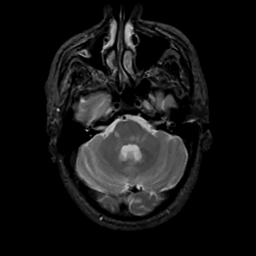

MR Study #10, April 28, 1991 -- Slice #12